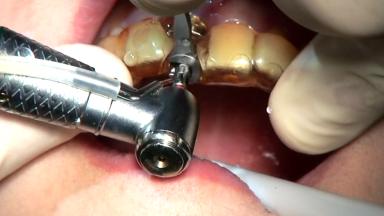

Immediate Implant - Immediate Temporary: Guided Surgery in the Esthetic Zone

In this video Dr. Nikos Mattheos demonstrates the full diagnostic, planning and treatment sequence of an immediate implant with an immediate prefabricated provisional restoration in the esthetic zone. A 28 years old female patient presents with discoloration and increasing mobility of tooth 11. Advanced stage of external resorption is diagnosed. Patient's high esthetic demands combined with intact gingival architecture and periodontal health makes her a good candidate for immediate placement and restoration to preserve the gingival contour. Surgical and restorative treatment is planned with digital workflow based on data from CBCT and intraoral scan. An immediate temporary crown is manufactured for placement at the day of the surgery. Flapless extraction is performed, and the implant placed with guided surgery. Consequently, the buccal gap of the socket is augmented with Xenograft, while the soft tissue space maintained with a collagen plug. Finally, a provisional crown is immediately placed on the implant with a titanium temporary abutment and an emax prefabricated crown.

• identify the main surgical steps and procedures involved in extraction and flapless implant placement in the anterior maxilla